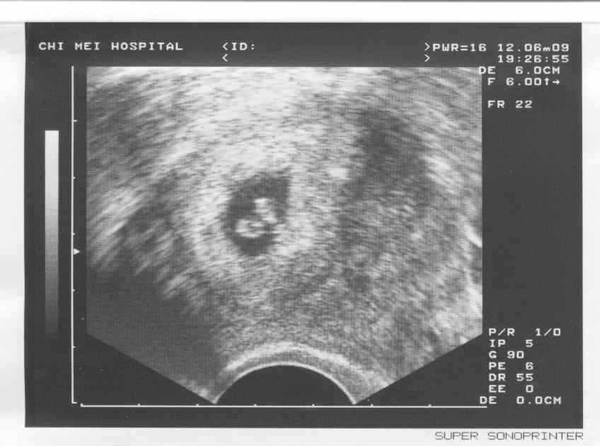

不過終於看到二寶的心跳很開心!

明天就帶著超音波照片去新加坡吧!老公一定也很開心!

20090612二寶.JPG